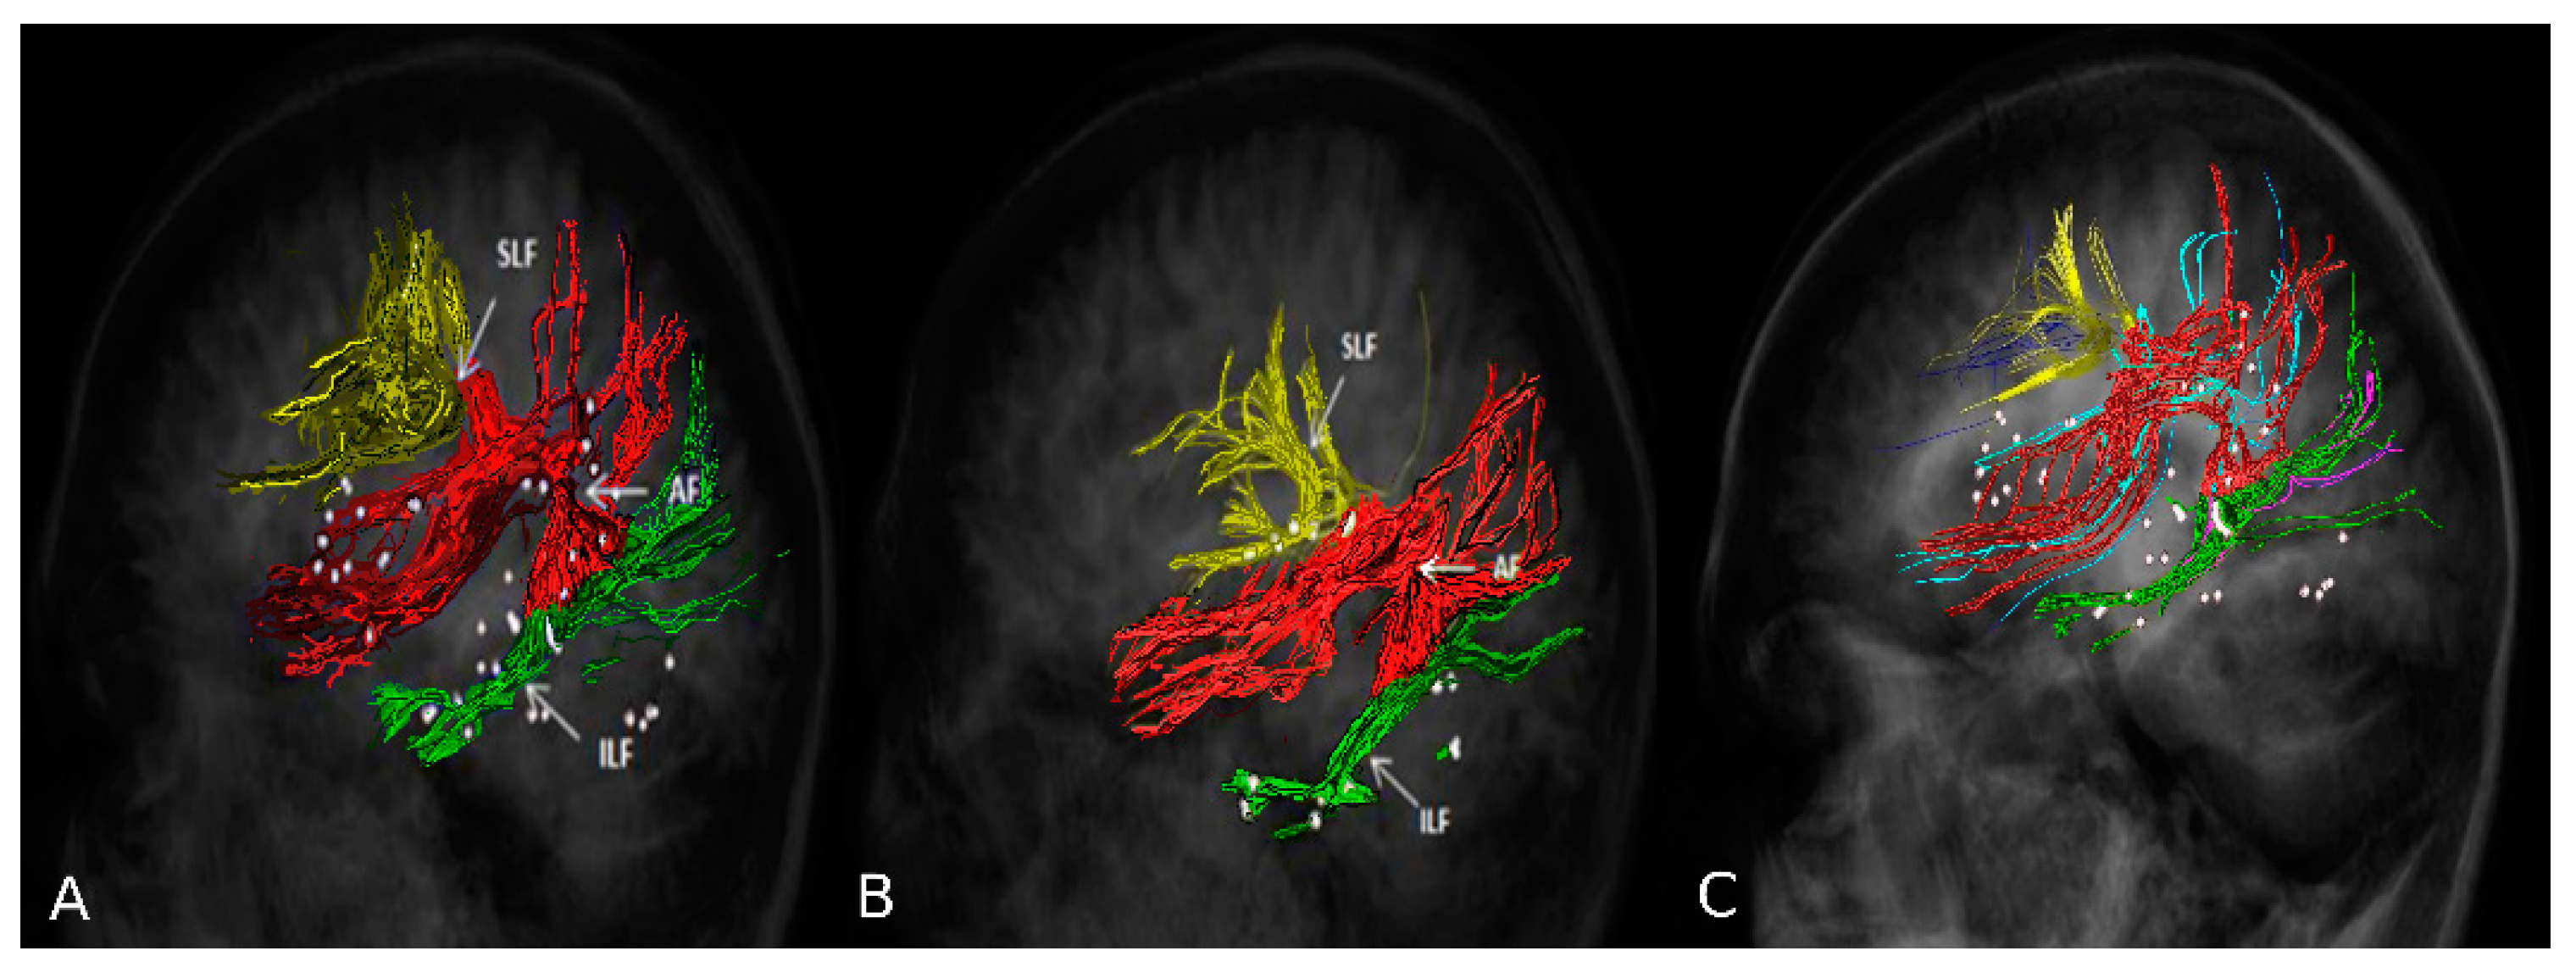

2.6. nTMS Based DTI-FT of Language Pathway

2.7. Presurgical Planning